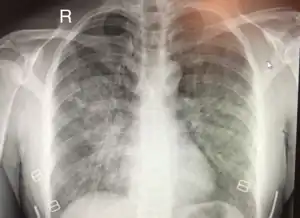

Chest x-ray of HAPE showing characteristic patchy alveolar infiltrates with right middle lobe predominance.

Hypoxic pulmonary vasoconstriction (HPV) occurs diffusely, leading to arterial vasoconstriction in all areas of the lung. This is evidenced by the appearance of "diffuse," "fluffy," and "patchy" infiltrates described on imaging studies of climbers with known HAPE.[9]

On physical exam, increased breathing rates, increased heart rates, and a low-grade fever 38.5o (101.3o F) are common.[9][10] Listening to the lungs may reveal crackles in one or both lungs, often starting in the right middle lobe.[9][10] This can be seen on X-ray and CT imaging of the chest.[9][10] One distinct feature of HAPE is that pulse oximetry saturation levels (SpO2) are often decreased from what would be expected for the altitude. People typically do not appear as ill as SpO2 and chest X-ray films would suggest.[9][10] Giving extra oxygen rapidly improves symptoms and SpO2 values; in the setting of infiltrative changes on chest X-ray, this is nearly pathognomonic for HAPE.[10]